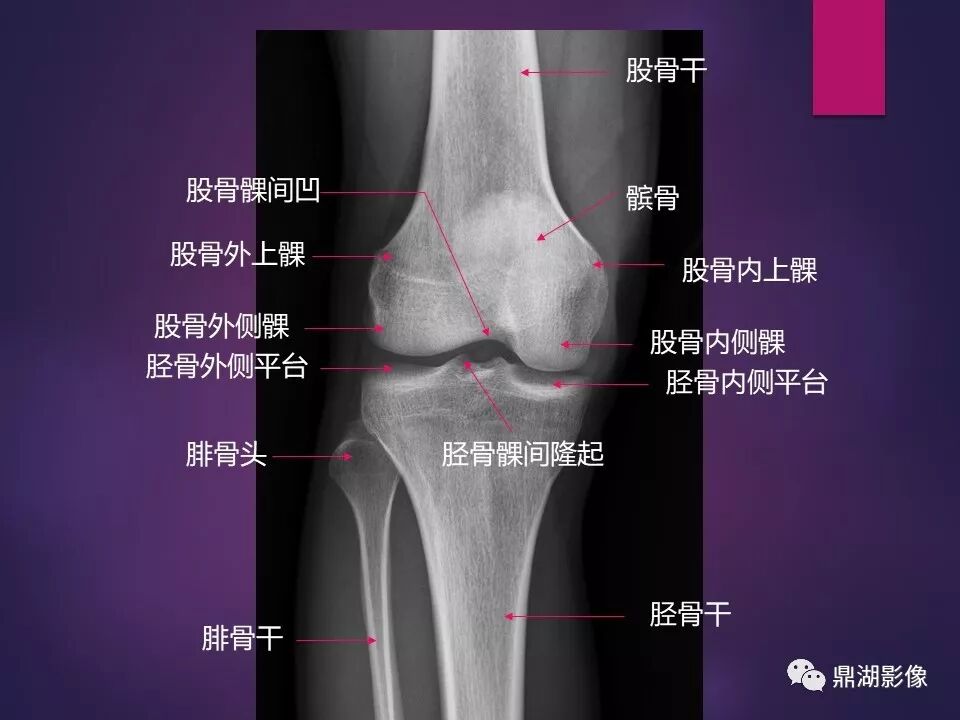

来源于:鼎湖影像 贵阳医学院医学影像系